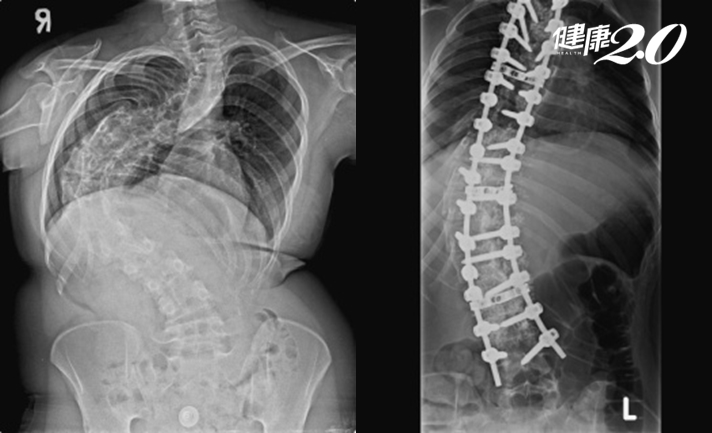

S形變C形!脊椎側彎高達128度

還有一位19歲少女,從小就診斷自發性脊椎側彎,曾經嘗試過物理治療、穿背架矯正但效果不理想,脊椎側彎角度持續惡化到128度,不僅活動能力下降,也時常感到呼吸困難、消化不良、食慾變差,再加上身體各部位關節、肌肉疼痛,讓她的日常生活備受困擾。

台中榮民總醫院腦腫瘤科主任楊孟寅說明,脊椎在正常發育下,會形成頸椎前凸、胸椎後凸、腰椎前凸、薦椎後凸的自然角度;從人的背面看脊椎是一直線,從側面看則是均勻的S形,這名少女的脊椎角度卻和常人不同,屬於胸腰椎大角度C形側彎,合併脊椎旋轉。

▲ 19歲患者的胸腰椎呈現大角度C形側彎。